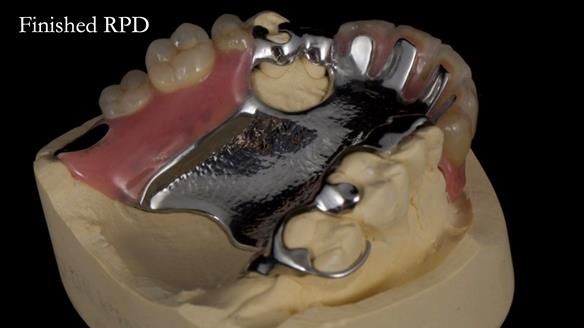

Keith’s case was one of the most challenging and rewarding cases I’ve treated this year. This 64 year old man presented with ill-fitting acrylic partial dentures that lacked stability, retention, and aesthetics. They constantly broke. He had lost the upper front teeth in a road traffic accident in his early 20s. The unopposed teeth had erupted, taking up space. After careful planning, we made a durable, metal-based upper partial denture/splint to address his dental concerns. He loved the outcome.

1. Denture design: A custom cobalt-chromium framework was Scandinavian-designed to maximise stability, protect the remaining teeth, and allow for future additions if needed.

2. Onlay preparations: Composite onlays were fitted for his upper left premolars to repair these teeth and support the new denture.

Keith’s denture incorporated a Duracetal shell clasp on upper right first premolar (Myerson), which are designed to be virtually visible, providing a more aesthetic solution while enhancing patient comfort. The Scandinavian-inspired approach, based in modern removable prosthodontic techniques, ensured the denture was not only durable but also visually pleasing. Additionally, the design was carefully planned to allow for future modifications, ensuring that if Keith loses additional teeth, the denture can be adapted rather than replaced entirely.

I also used the Dahl concept to re-establish the occlusion upon fitting the RPD, which helped to intrude the lower left canine without needing to grind it too much.